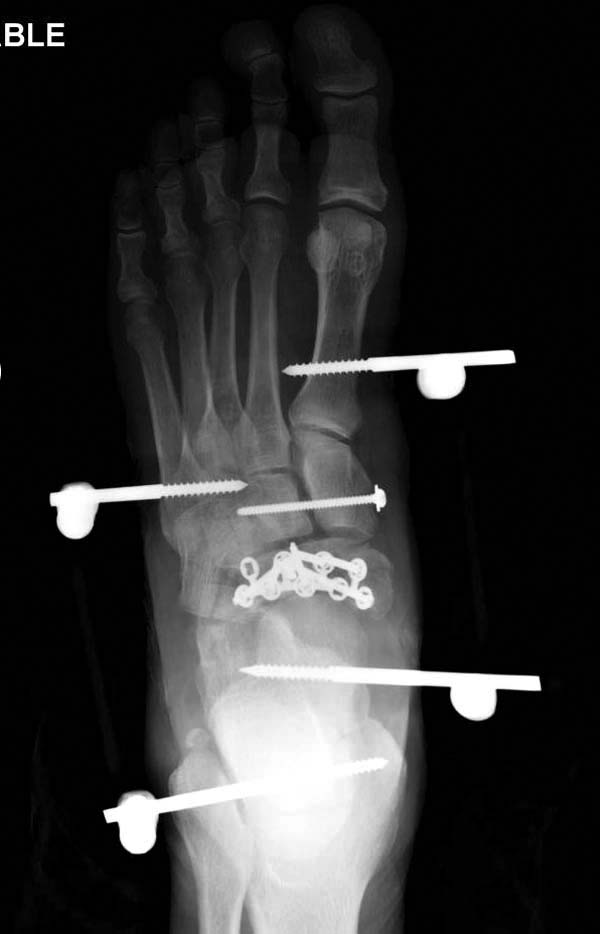

До лечения, в процессе, через 8 мес.

Современную тактику лечения переломов пилона описали коллеги, а мне остается подтвердить клинически. В многоэтапном лечении главное - это предупреждение сокращения мягких тканей, от которого зависит судьба конечности. Дистракция любым наружным фиксатором, и по готовности мягких тканей - премежуточная или окончательная фиксация.

В нашем случае, травма в результате коллапса крыши. Открытый перелом. Ургентные Irrigation and Debridment, дистракция наружным фиксатором. В госпиталях первого уровня редко бывает изолированная травма, и на другой стороне повреждение стопы с переломом навикулярной кости. После обработки раны - вакуум и двухсторонние наружные фиксаторы.

Через три дня повторная I&D, где через рану манипулировали дистальным фрагментом с установкой пары межфрагментарных шурупов. На рану вакуум и следующая обработка закончилась закрытием раны. Отек держался немного дольше, чем обычно.

После спадения отека вариантов фиксации много, включая мининвазивную технику, но данный случай закончили установкой простого аппарата Илизарова.

Через три дня оперирована стопа и для нейтрализации сил колонн оставили наружный фиксатор.